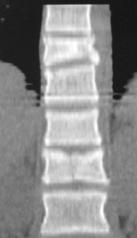

При переломах двух и более смежных позвонков устанавливали более протяженную фиксацию с опорой на интактные тела позвонков относительно травмированных. При многоуровневых повреждениях (травма двух и более позвонков, находящихся друг от друга на расстоянии минимум двух позвоночно-двигательных сегментов), использовали раздельную фиксацию каждой зоны, сохраняя подвижный сегмент между ними (рис. 11, 12).

Рис. 11. Рентгенограммы пациента С. 16 лет Взрывной перелом L1, L4, L5

А – до операции; Б – после транспедикулярной репозиции и фиксации Th12-L2, L3-S1 и заднего локального спондилодеза |